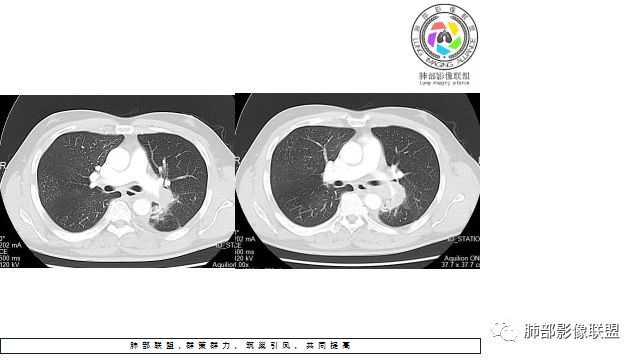

1.左下肺门区巨大肿块,支气管显示不清,轻度阻塞性炎症,没有明显肺不张,提示管腔受压狭窄可能性大于堵塞,这较少见于鳞癌。

2.病灶边缘光滑,未见明显分叶、毛刺,未见明显强化,这符合腺癌影像学特点,却符合神经内分泌癌表现。

3.病灶内密度均匀,轻到中度均匀强化,大病灶未见明显液化坏死区及空洞,不符合鳞癌而符合小细胞肺癌特点。

4.病灶内有肺动脉走形,血管局部受压,未见破坏,病灶乏血供,呈血管包埋或血管造影征;侵袭性力强及破坏力弱、血管漂浮都符合SCLC,所以鳞癌的可能性也不大。

5.左肺门块影或淋巴结肿大,竭力挤兑肺门血管结构,呈冰冻肺门;有时候SCLC可以单独呈现冰冻肺门,而没有没有冰冻纵隔。